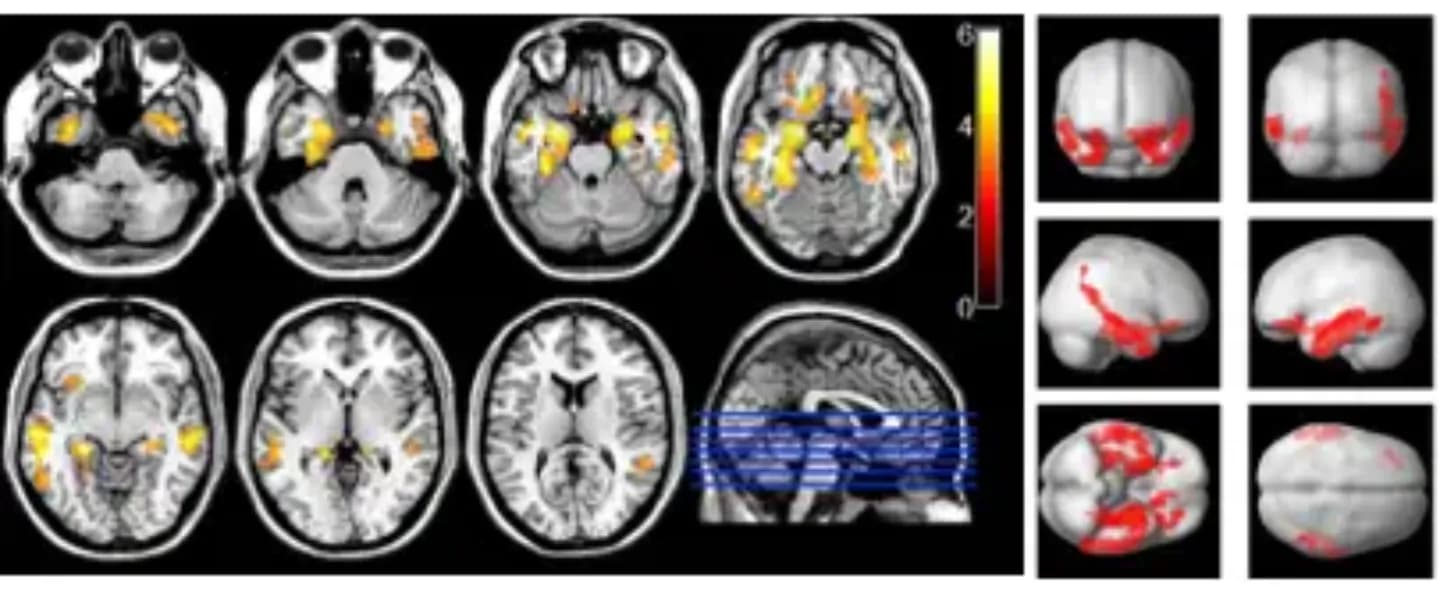

Los probióticos parecen ayudar a restaurar este equilibrio y mejorar la función cognitiva, según una investigación